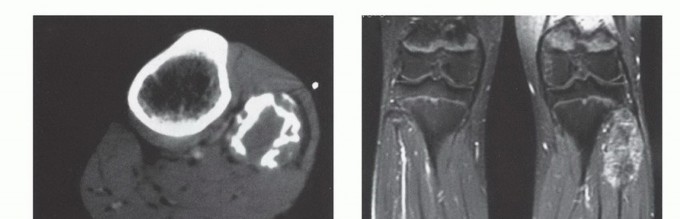

الدراسات التصويرية

تُعد الدراسات التصويرية حجر الزاوية في تشخيص أورام الشظية وتحديد مرحلتها:

- الأشعة السينية العادية (Plain Radiographs): تُظهر الأشعة السينية مدى تدمير العظم، ومدى انتشار الورم داخل العظم، وأي اختراق للقشرة العظمية.

- التصوير المقطعي المحوسب (Computed Tomography - CT): يوفر التصوير المقطعي صورًا تفصيلية للعظم، مما يساعد في تقييم مدى تدمير العظم وانتشاره داخل نخاع العظم. كما أنه مفيد لتقييم امتداد الورم إلى الأنسجة الرخوة المحيطة.

- التصوير بالرنين المغناطيسي (Magnetic Resonance Imaging - MRI): يُعد التصوير بالرنين المغناطيسي الأداة الأفضل لتقييم امتداد الورم إلى الأنسجة الرخوة المحيطة، وتحديد علاقته بالأعصاب والأوعية الدموية، وتقدير حجم الورم بدقة. كما أنه يوضح الامتداد داخل نخاع العظم بشكل ممتاز.